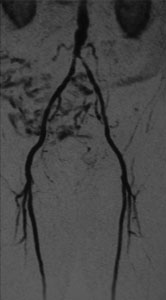

症例8 MRA

Bilateral CIA Stenting (Kissing stent with Palmaz stent)

ABI:右1.0 左0.6

【治療計画】